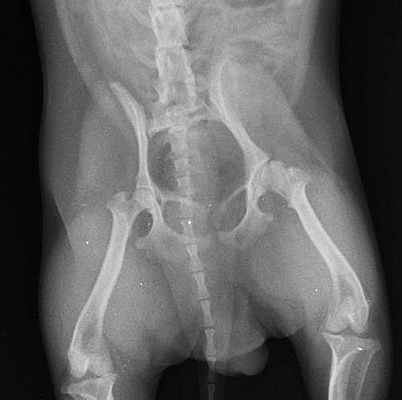

Рентгенограмма собаки с болезнью Легга -Кальве-Пертеса. Пораженный сустав справа